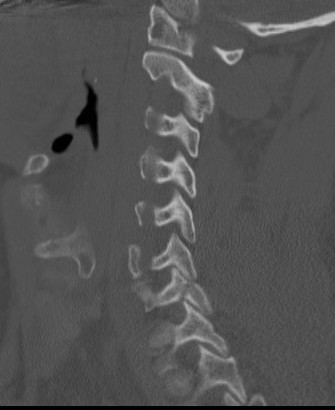

Superior articular process fracture

Inferior articular process fracture

Stability

- larger fragments at risk (> 40% of the lateral mass)

< 40% of the lateral mass

Superior articular facet fracture approximately 50% of the lateral mass